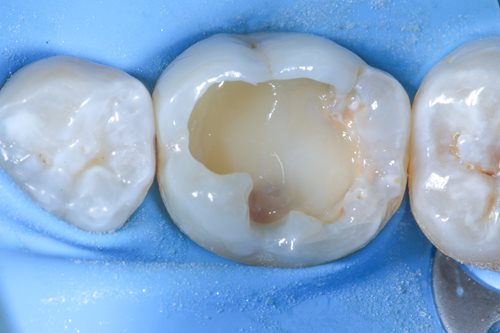

After selective etching and the composite shaping took place with hand instruments and a small brush. He used tooth colours to create realistic depth of colour and let the filling look like a natural, healthy tooth surface. As a last step, he polished the whole treatment area and performed a bite test. The positive result marked the end of a completely successful treatment.

Having completed the endodontic treatment successfully, Dr. Benjamin was able to preserve his patient’s tooth and prevent tooth loss. Thanks to the BioRepair putty material, the vitality of his patient’s tooth could be preserved, and the application of tooth colours ensured an aesthetically pleasing result.